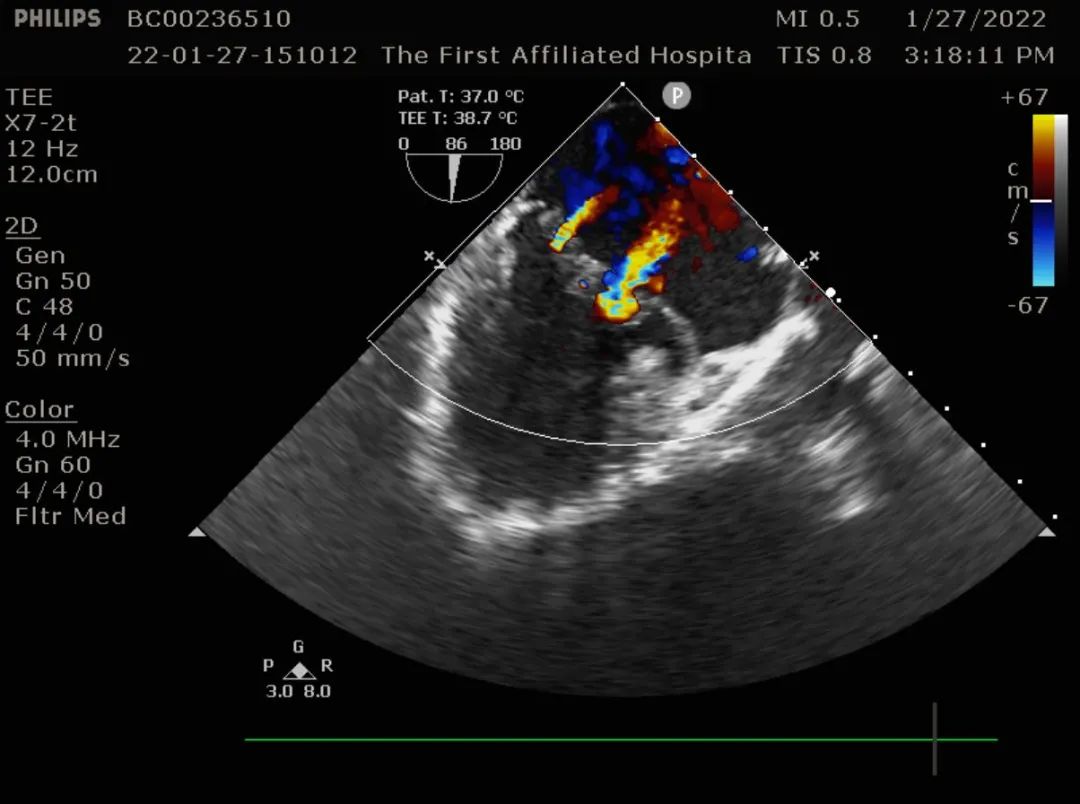

二尖瓣后叶脱垂,大量返流

术中食道超声提示二尖瓣瓣叶冗长,组织增厚,多处返流。提示barlow综合征可能。

术中食道超声监测

术中超声检测提示二尖瓣瓣叶对合良好,瓣叶对合高度1cm,未见明显返流。房间隔缺损修补术后,未见残余漏。术中及术后未出现相关并发症,手术圆满完成。患者已脱机拔管,转回普通病房,拟年前出院。